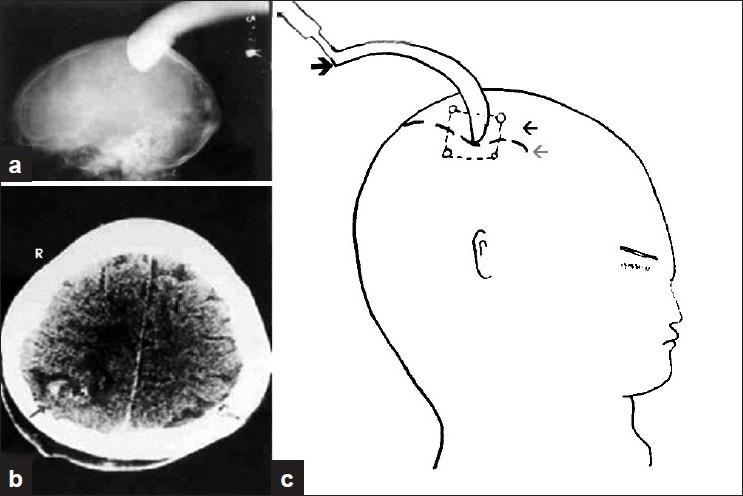

Low velocity penetrating head injury with impacted foreign bodies in situ.

Penetrating head injury is a potentially life-threatening condition. Penetrating head injuries with impacted object (weapon) are rare. The mechanism of low velocity injury is different from high velocity missile injury. Impacted object (weapon) in situ poses some technical difficulties in the investigation and management of the victims, and if the anticipated problems are not managed properly, they may give rise to serious consequences. The management practice of eight patients with impacted object in situ in context of earlier reported similar cases in literature is presented.